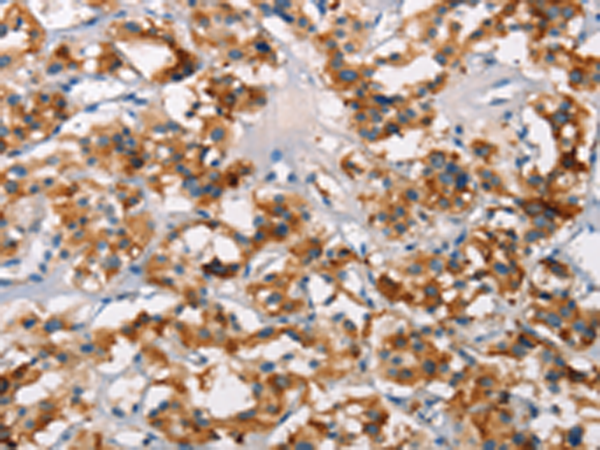

分类: 科研抗体货号: P11573别名: HYDM; PAN7; NALP7; NOD12; PYPAF3; CLR19.4应用: IHC反应种属: Human